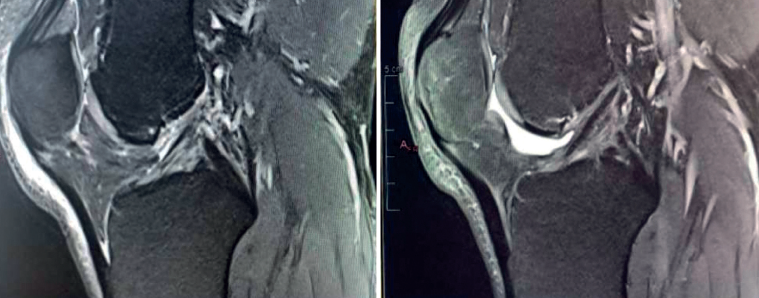

The main indication for primary ACL repair is in patients with high-grade complete or partial tears corresponding to types 1 or 2 of the original Shermanclassification(7), i.e. in avulsions of the femoral insertion (type 1) or in proximal tears leaving 75-90% of the distal ligament intact (type 2). In any case, good quality of the remaining tissue is essential. It should be noted that the incidence of tears of this kind appears to be greater in individuals over 35 years of age(7). This is not a problem, given that the incidence of re-rupture following ACL repair is higher in younger patients under 21 years of age(8,9).

With regard to the timing of surgery, the operation is ideally performed within 6 weeks of the injury(10,11,12), although good results have also been published repairing chronic tears in which the torn ACL stump heals over the posterior cruciate ligament (PCL)(13,14).

We now know from the histological study of ACL remnants after rupture that the ligament has some intrinsic capacity for spontaneous healing, as evidenced by the presence of vascular buds, nerve endings and cells with healing capacity in the remnant tissue(3). Further evidence of this self-repairing capacity can be found in the good functional results published in some patients treated on a conservative basis, especially older individuals with lesser physical demands(4)(Figure 1).

Despite this, it is true that complete healing of the ACL without surgical treatment after rupture is rare. Among other reasons, this is because of the presence of synovial fluid inside the joint, which hinders the formation of a contained hematoma between the two extremities of the torn ligament (a necessary preliminary step for tissue healing). To overcome this adverse joint environment and improve the results of ACL reconstruction, a number of authors(5) have for some years recommended preserving the remains of the torn ligament, taking advantage of its biological capacity to facilitate its integration into the bone tunnels and improve proprioception.